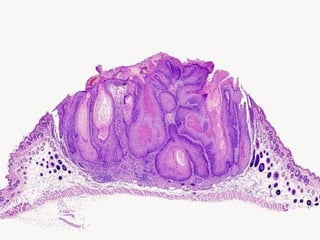

• #43 Keratoacanthoma, the MAIN lesion to differentiate from squamous cell carcinoma

• #44 Keratoacanthoma, the MAIN lesion to differentiate from squamous cell carcinoma

• #45 Keratoacanthoma, the MAIN lesion to differentiate from squamous cell carcinoma. What is a collarette? Is a collarette the classical feature which differentiates KAs from SCCs? Ans: YES